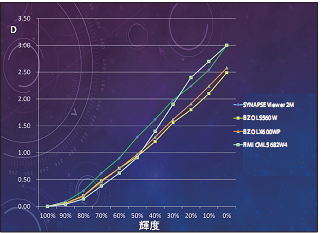

各大型モニタにSMPTEパターンを表示し、輝度

100~0%の明るさをX線フィルムの濃度を測定

するDensitometerで計測した。輝度100%を

Density0とし、輝度10段階の各明るさを

Densityで表示した。

今回、当院にある3台の4×2K大型モニタであるEIZO LX600WP(60インチ)、EIZO LS560W(56インチ)、FIMI CML5682W4(56インチ)、およびSYNAPSE Viewer2Mの濃度、輝度、特性を比較してみた(図1)。各モニタにより特性曲線が異なっており、EIZOのモニタでは直線階調が用いられており、FIMIではX線フィルムに近い非線形の階調が用いられていた。最高黒レベルにも差がありLS560WとLX600WPはそれぞれDensity:2.4

とDensity:2.6、FIMICML 5682W4とSYNAPSE Viewer2MではDensity:3.0であった(図2)。